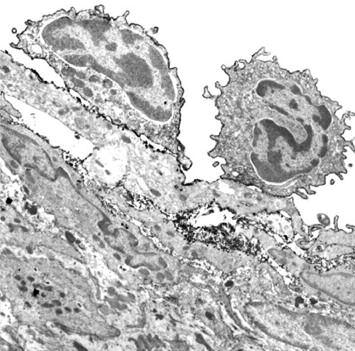

Un altro processo durante il quale ha luogo la digestione del collagene è in caso di infezione. La difesa del corpo contro gli invasori (microbi) è assicurata dai globuli bianchi presenti nel sangue. Diversi sottogruppi di globuli bianchi svolgono funzioni specifiche del sistema immunitario, meccanismo di “difesa” a livello cellulare.

Particolarmente importanti sono i macrofagi, che possono ‘mangiare’ e digerire gli invasori. Forme immature di queste cellule, chiamate monociti, possono raggiungere ogni parte del corpo attraverso il flusso sanguigno. Se l‘infezione avviene nei polmoni, il corpo secerne ’sostanze di emergenza' che attraggono i monociti nel luogo dell’infezione.

In caso di infezione polmonare, i globuli bianchi, che giungono con il flusso del sangue, attraversano la parete dei vasi sanguigni, piccoli capillari polmonari, per trasferirsi poi nel tessuto polmonare, con l'aiuto di enzimi che dissolvono il collagene. Per raggiungere il sito dell’infezione nei polmoni (ad esempio, batteri o virus), i globuli bianchi devono essere in grado di migrare attraverso il tessuto polmonare Per far ciò, utilizzano lo stesso meccanismo per sciogliere il collagene, allentando il denso tessuto connettivo circostante e spostandosi attraverso il tessuto in modo molto simile descritto nel paragrafo precedente, la produzione di collagenasi agisce come un machete usato per aprire un varco attraverso la giungla.

Subito dopo che i globuli bianchi sono migrati e hanno raggiunto il punto nel quale é in corso un’infezione ,il tessuto connettivo si richiude, utilizzando meccanismi che neutralizzano gli enzimi e riparano i tessuti.

Questa riparazione è garantita da un’adeguata disponibilità di fattori neutralizzanti le collagenasi, ‘pacman’, provvedendo alla produzione di nuove molecole di collagene.

Es.: Infezione polmonare

I globuli bianchi (il sistema di difesa del nostro corpo) lasciano un piccolo vaso dei polmoni per spostarsi con l’aiuto delle collagenasi nel focolaio dell’infezione

Subito dopo la migrazione dei globuli bianchi si blocca la produzione delle collagenasi e si ripara il tessuto connettivo.

In normali condizioni fisiologiche i globuli bianchi utilizzano le collagenasi per una durata di tempo ben preciso, determinato dalla funzione (difesa immunitaria) che svolgono.

Ab) Le cellule bianche del sangue lasciano il flusso sanguigno e, con l‘aiuto di enzimi che digeriscono il collagene, penetrano all'interno della parete dei vasi sanguigni.

a) Un globulo bianco dal flusso di sangue (area bianca) si attacca al rivestimento delle cellule (cellule endoteliali) della parete dei vasi sanguigni.

Cd) Le cellule bianche del sangue hanno iniziato la loro migrazione attraverso il tessuto connettivo che ora ne è completamente circondato

Copyright Dr A Loesch, immagini autorizzate

c) I globuli bianchi ora hanno abbandonato completamente il flusso sanguigno e la parete dei vasi sanguigni è ben chiusa alle loro spalle.